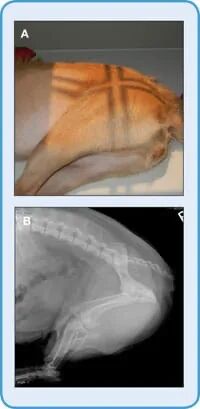

图2.大型犬的侧位x光片(A)整只犬的右侧x光片。(B)准直器和指示腹部x光照片颅边界的手。(C)准直器和指针在大转子水平上指示右侧腹部侧位片的尾部边界。(D)右侧前腹部x光片;注意肋骨头(胸椎)和腰椎横突的重叠。(E)叠加横突的特写(白色箭头)。(F)D中犬尾侧腹部的右侧;两幅图像有重叠(包括L1-L3 ),尾侧腹部x光片已经校准到大转子的水平。注意髂骨翼和腰椎横突的重叠。(G)前腹部左侧x光照片;注意气体是如何从右侧侧位片的胃底位置转移到左侧侧位片的幽门位置的。